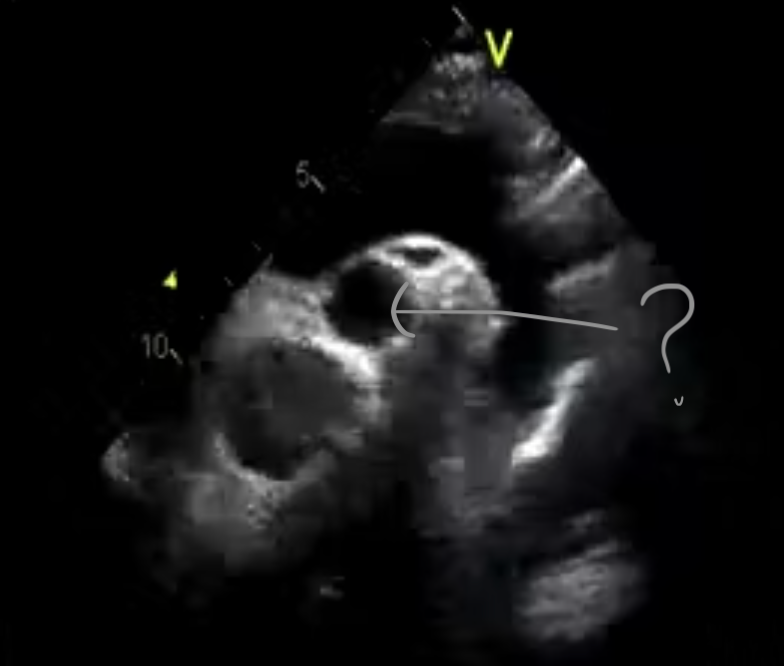

Q

The arrow (gray one) in this image is pointing to the:

A

Left main coronary artery

*the image demonstrates the left coronary artery originating from the left coronary cusp